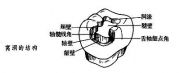

| 2021年7月26日 (一) 20:03 | 窝洞的结构.jpg (文件) |  |

11 KB | Uploaded with SimpleBatchUpload | 3 |